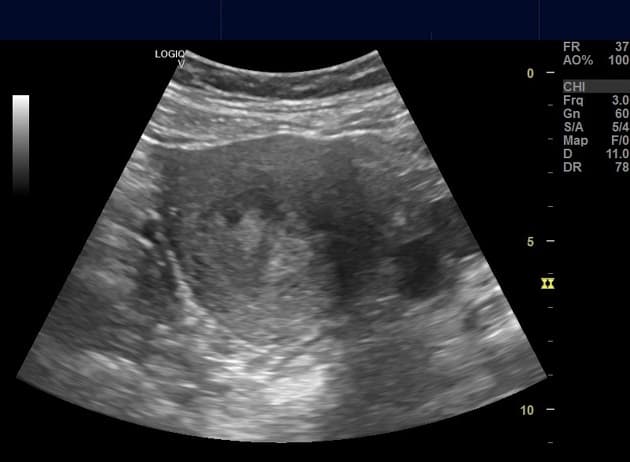

Polyp nội mạc tử cung

» Thông tin: Nữ giới – 40 tuổi.

» Lâm sàng: Rong kinh.